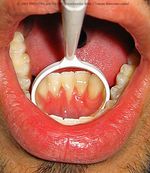

When jewelry, generally labret and lip piercings, but also from tongue piercings rests against your gums, there is erosion over time. Just like water dripping on rock can dig a hole over years, a piece of metal rubbing on your gums can rub a hole in your gums, exposing the roots of your teeth.

Think that the roots of your teeth aren't covered of enamel.

Obviously, this puts you at dramatically increased risk of gum and tooth disease, and risks the loss of the affected teeth altogether. Expensive surgery (gum grafts, where gum is removed from one part of your mouth and transplanted into the damaged area, generally start at over $500) is needed to correct this problem, so if you notice it starting, (again), deal with it immediately. One reader writes about their medical bills,

This risk can be minimized with careful choice of jewelry (determined by the shape of your anatomy) — although other factors such as smoking, diet, and even just genetics also play a role. A professional piercer can help you with this, including suggesting alternative jewelry if your gums are being eroded by what you are wearing. Please note that when this happens it is generally irreversible so don't let it progress if you notice it!!!